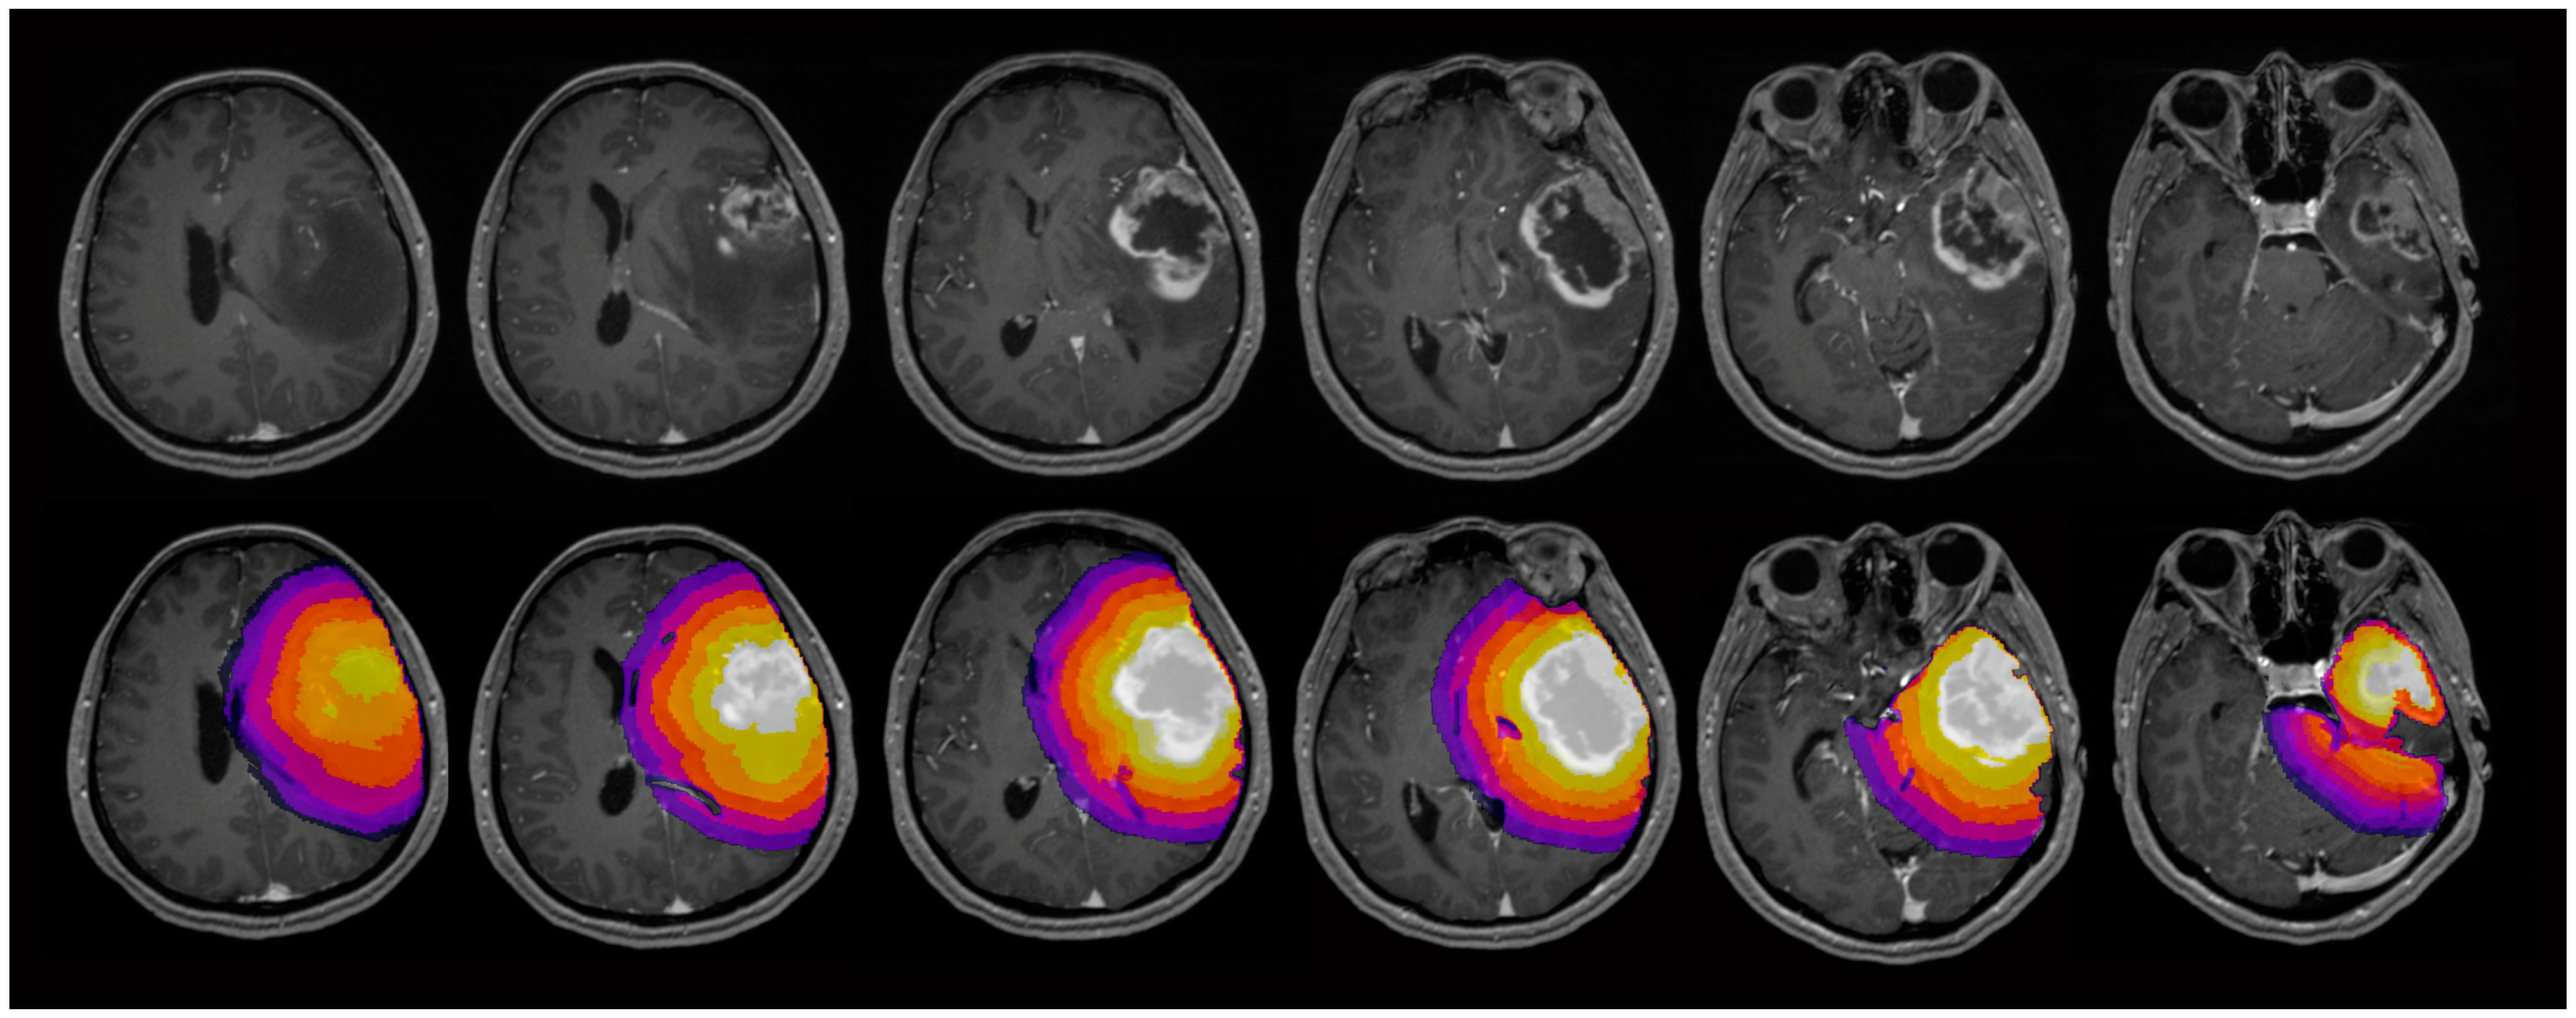

2.4. Image Analysis